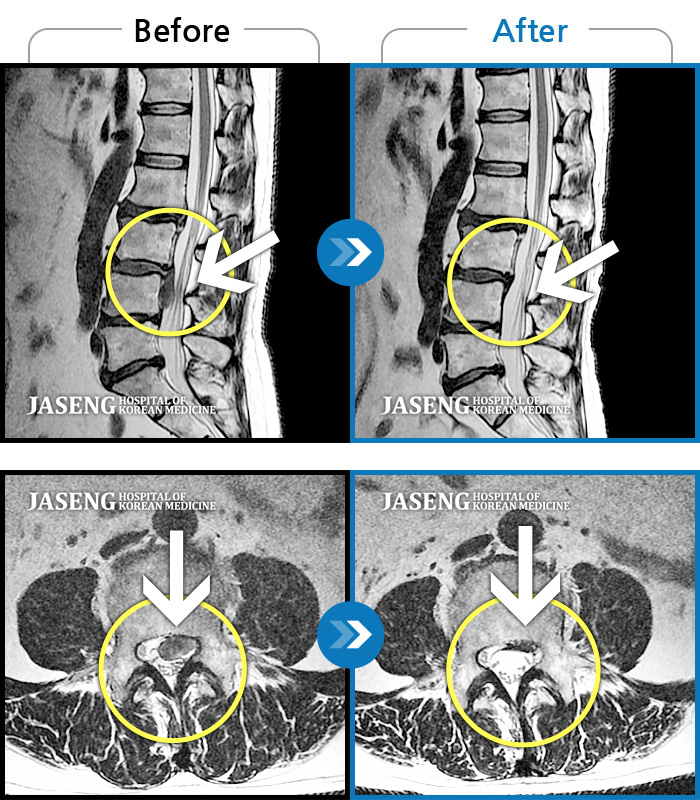

MRI 치료사례

허리디스크로 인한 보행시 통증 및 다리 근력 저하